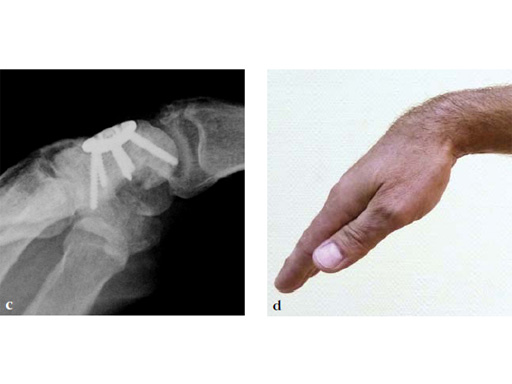

Fig 7ab No impingement of the plate against the dorsal rim of the radius in extension.

The VA-locking plate holes accept both 2.4 mm cortex and VA locking screws. The use of cortex screws provides the option for compression by pulling the bone to the plate and locking screws enhance fixation in cancellous bone. The result is an extremely rigid construct that can withstand the strains of early postoperative mobilization. Midcarpal fusion provides a functional wrist motion achieving a minimum of 30° extension, 30° flexion, and 30° combined ulnar-radial deviation. This '30° rule' enables the patient to perform up to 90% of daily living activities.